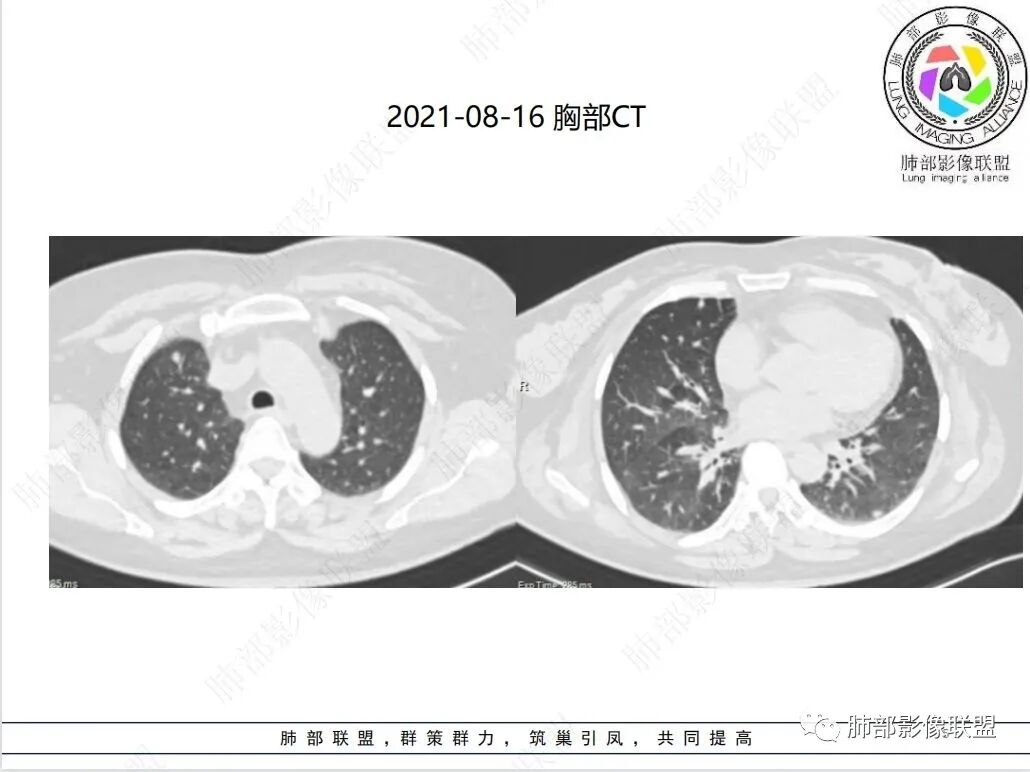

双肺马赛克征,双肺下叶结节影及左肺下叶实变影,小叶间隔增厚,血管增粗,合并有鼻窦炎及肾功能不全,抗感染无吸收,考虑结缔组织病相关肺病

3. 病灶在外周胸膜下为主,小叶间隔增厚,支气管壁增厚,部分细支气管可见闭塞,左肺下叶实变影。合并有鼻窦炎及肾功能不全,抗感染无吸收。

ANCA相关性血管炎肺部常被累及。最常见的为肺部结节,其中以支气管周围结节最多,其次是支气管扩张和胸腔积液以及肺出血和淋巴结肿大、肺气肿和空洞样病变等。由于肺内磨玻璃影、纤维条索影、斑片实变影、肺结节、网格状影、蜂窝状影、 肺大泡影、肺气肿、空洞、胸膜增厚、胸腔积液、 心包积液、纵膈淋巴结肿大等多种表现存在,极易误诊为肺部感染性疾病、间质性肺炎、肺结核及肺栓塞等疾病。